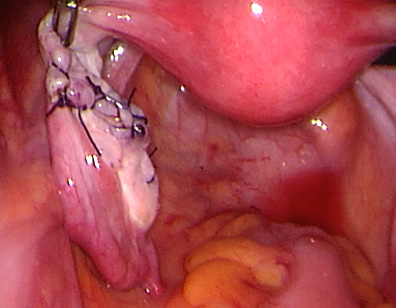

The products of conception are removed completely from the tube.

The tube was closed back and reconstructed. If a pregnancy ectopic is suspected early, laparoscopic surgery may help to preserve the tube involved.